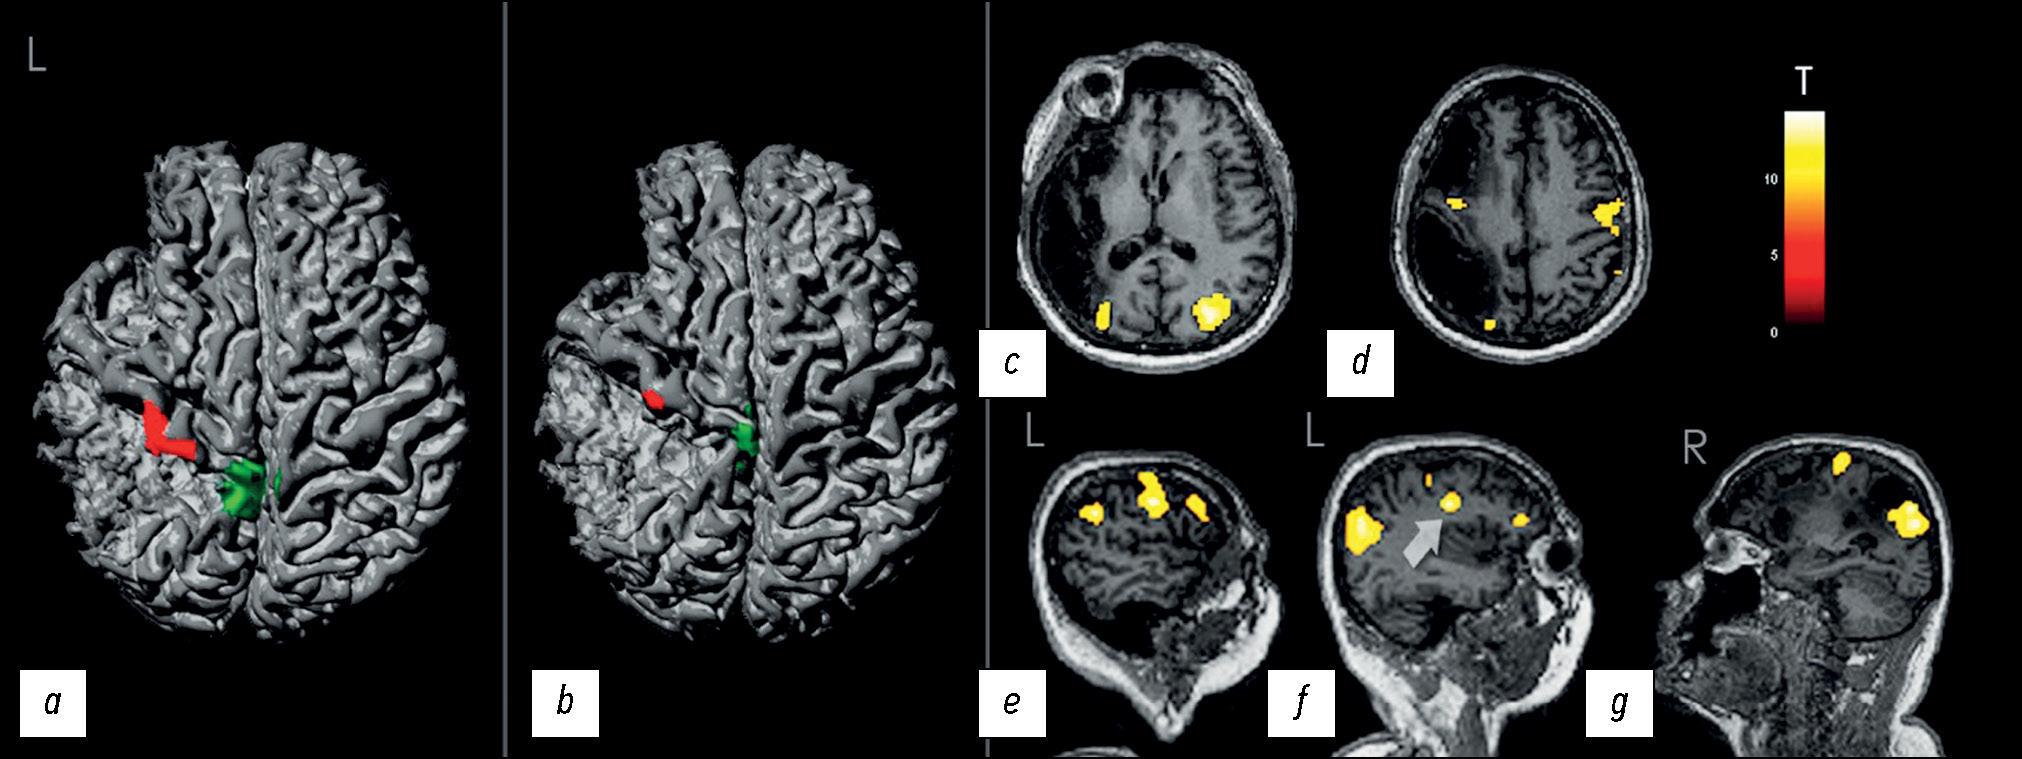

В результате тестов, направленных на активацию моторных зон левых конечностей, предполагаемые очаги активации оказались локализованы обычно — в сохранной правой прецентральной извилине (рис. 4, a), согласно сведениям о корковой проекции чувствительной и двигательной систем по W. Penfield [9]. При тактильной стимуляции определялись признаки активации зон в дорзальных отделах прецентральной извилины (рис. 4, b), смежных проекциям классического распределения в постцентральной извилине, которая у пациента была субтотально поражена.

Рис. 4. a, b — трёхмерные реконструкции данных функциональной магнитно-резонансной томографии: a — при движении пальцами левой кисти и левой стопой; b — при тактильном раздражении левой кисти и левой стопы; красный цвет соответствует кисти, зелёный — стопе. c, d, e, f, g — магнитно-резонансные томограммы с данными функциональной магнитно-резонансной томографии о локализации зон активации во время устного счёта без произношения вслух в аксиальной плоскости (c, d), сагиттальной плоскости с визуализацией левого (e, f) и правого (g) полушарий. Стрелкой указано возможное пересечение с зоной Брока.

Во время устного счёта без произношения вслух визуализировался очаг активации, преимущественно расположенный в средней и частично нижней лобных извилинах левой лобной доли (рис. 4, c–g); также отмечался мелкий очаг активации в сохранной части средней лобной извилины справа (рис. 4, f) и симметричные очаги в правом и левом предклиньях (рис. 4 c, e, f, g).

В описываемом случае нижняя лобная и большая часть средней лобной извилин правого полушария были поражены, и, по данным фМРТ, признаков их активации не определялось (в средней лобной извилине — имелись лишь минимально). В нижней лобной извилине слева одна из зон предполагаемой активации (рис. 4, f, отмечено стрелкой) частично перекрывалась с зоной Брока [21], что можно объяснить вовлечением речевого центра в силу мысленного использования слов в процессе вычисления.